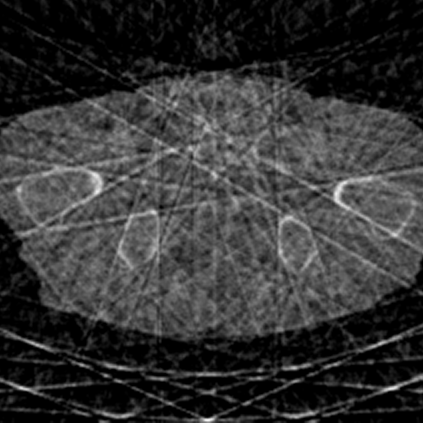

Sparse-view computed tomography (CT) -- using a small number of projections for tomographic reconstruction -- enables much lower radiation dose to patients and accelerated data acquisition. The reconstructed images, however, suffer from strong artifacts, greatly limiting their diagnostic value. Current trends for sparse-view CT turn to the raw data for better information recovery. The resultant dual-domain methods, nonetheless, suffer from secondary artifacts, especially in ultra-sparse view scenarios, and their generalization to other scanners/protocols is greatly limited. A crucial question arises: have the image post-processing methods reached the limit? Our answer is not yet. In this paper, we stick to image post-processing methods due to great flexibility and propose global representation (GloRe) distillation framework for sparse-view CT, termed GloReDi. First, we propose to learn GloRe with Fourier convolution, so each element in GloRe has an image-wide receptive field. Second, unlike methods that only use the full-view images for supervision, we propose to distill GloRe from intermediate-view reconstructed images that are readily available but not explored in previous literature. The success of GloRe distillation is attributed to two key components: representation directional distillation to align the GloRe directions, and band-pass-specific contrastive distillation to gain clinically important details. Extensive experiments demonstrate the superiority of the proposed GloReDi over the state-of-the-art methods, including dual-domain ones. The source code is available at https://github.com/longzilicart/GloReDi.